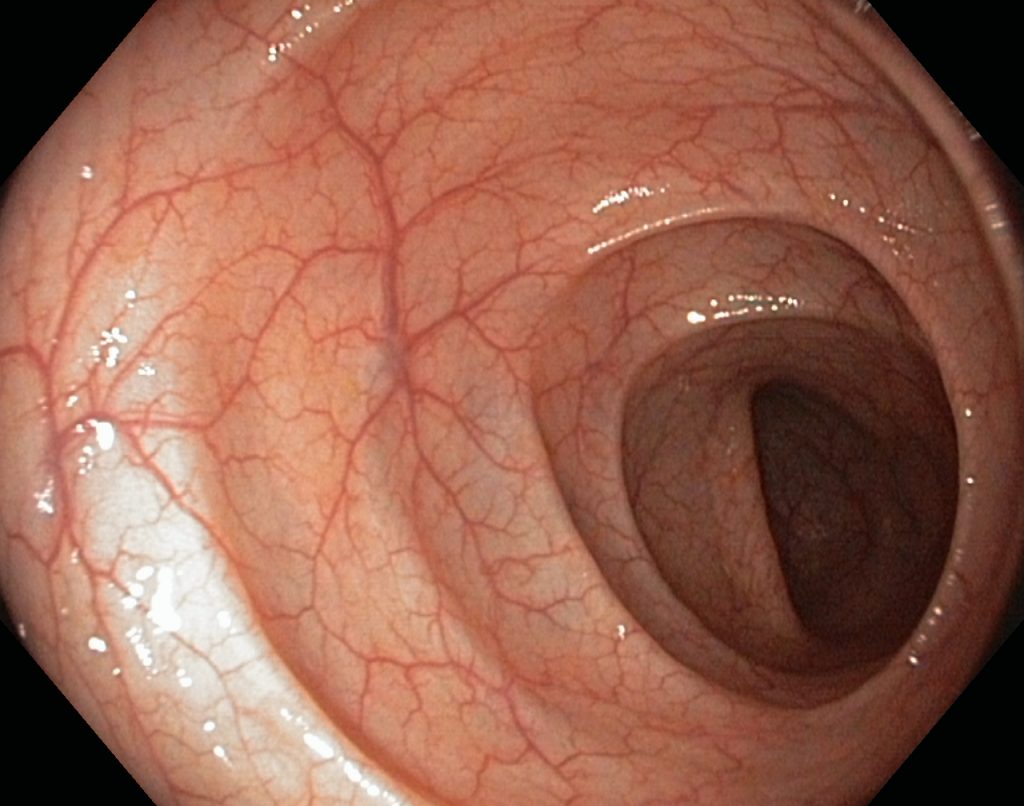

Here are some of the signs if a healthy colon: